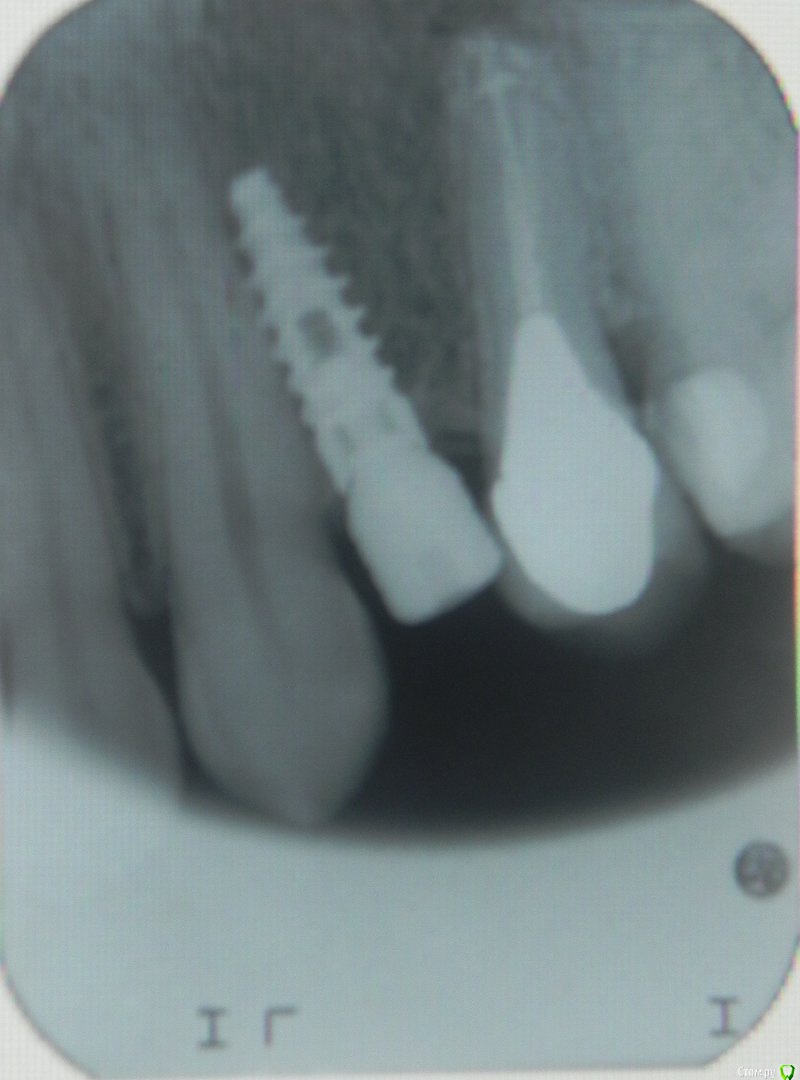

Tensergeyh Опубликовано 13 июня, 2015 Поделиться Опубликовано 13 июня, 2015 (изменено) Уважаемые коллеги, вот такая ситуация с имплантом в области 36. Ваше мнение, какие прогнозы? Хотел переустановить, пациентка категорически против, её ничего не беспокоит. Как поступить? http://s019.radikal.ru/i619/1506/19/267d0a7a6515.png Изменено 13 июня, 2015 пользователем Большой Зеленый Ссылка на комментарий

red_butler Опубликовано 13 июня, 2015 Поделиться Опубликовано 13 июня, 2015 сделайте несколько прицельных снимков, они Вас успокоят 2 Ссылка на комментарий

ILGAMSA Опубликовано 13 июня, 2015 Поделиться Опубликовано 13 июня, 2015 сделайте несколько прицельных снимков, они Вас успокоятне успокоили... 1 Ссылка на комментарий

АнтонТЛТ Опубликовано 13 июня, 2015 Поделиться Опубликовано 13 июня, 2015 Сделайте кт, может апексы имплантата с зубом под разными углами 2 Ссылка на комментарий